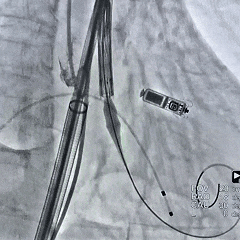

初始造影确定无冠窦,可见大量反流

瓣膜初始0位定位